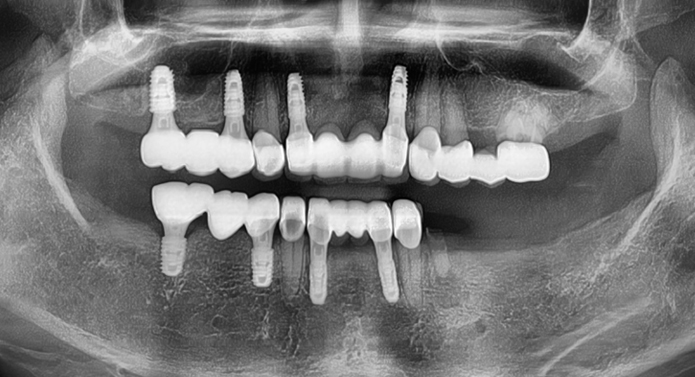

전체 임플란트는 상·하악 전체 치아가 상실되었을 때, 디지털 정밀 진단 → 최소한의 심기 → 고정형 보철 연결을 통해 자연 치아 기능과 심미성을 회복하는 디지털 기술력 기반의 치료입니다.

골 상태가 좋지 않아도 빠르게 고정되는 특수 나사 디자인

습기에 반응하는 초친수성 표면으로 골세포의 부착과 골유착을 획기적으로 향상

발치즉시, 즉시 부하, 뼈 질이 약한 고령환자까지 다양한 조건에서도 우수한 안정성 확보

전 세계 70개국 이상에서 사용되는 프리미엄 브랜드 SCI 논문 다수, 임상 연구로 효과 입증